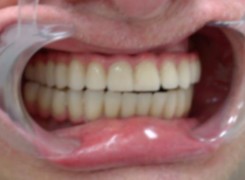

Pan Ryszard trafił do Naszego Gabinetu z jasno sprecyzowanym oczekiwaniem. Miał 84 lata i chciał odzyskać możliwość swobodnego spożywania posiłków oraz poprawienia sobie komfortu życia a także prosił aby przywrócić mu piękny uśmiech jakim cieszył się przed laty. Już na początku pierwszej rozmowy zastrzegł, że interesuje go wyłączenie rozwiązanie uzupełnieniem protetycznym stałym. Nie miał zamiaru użytkować żadnych protez ruchomych. Mając na uwadze powyższe wykonaliśmy Panu Ryszardowi zdjęcie pantomograficzne oraz badanie tomograficzne szczęki i żuchwy na postawie których zapanowywaliśmy Pacjentowi optymalne rozwiązanie – stałe uzupełnienie protetyczne w postaci 28 koron cyrkonowych zamontowanych do dwóch belek cyrkonowych które będą przymocowane do 16 implantów w konfiguracji 8 wszczepów w szczęcie 8 w żuchwie. Po omówieniu powyższego planu przystąpiliśmy do Wspólnej pracy której efekty w poszczególnych etapach prezentujemy poniżej.